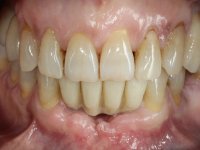

After an imaging study, the placement of two implants of 3.3 mm in diameter and 10 mm in length was planned. On the day of surgery, teeth 42 and 32 were extracted and the implant was removed. The implants were placed in the area of the alveoli, taking care to slightly lingualize their positioning. An impression was made using the open tray technique with the flap open for the fabrication of the immediate provisional bridge. While the impression was taken to the laboratory, tall healing screws were placed and the surgical wound was sutured. The patient waited 2 hours in the waiting room while the temporary bridge was made in the laboratory. An immediate screw-retained provisional bridge was placed and its seating was controlled by imaging. After 3 months, the final impression was made using an open tray technique. In this consultation, we took the opportunity to polish the temporary bridge with rubber cups so that the soft tissues could mature in better conditions. Information was collected to better characterize the monolithic structure in Zr. Color guides were used for the coronal and gingival ceramics. In the laboratory, a bridge was made in Zr. bolt-on that has been carefully characterized. After approval by the patient, it was definitively placed in the mouth. Tightening was performed with a dynamic wrench with a torque of 35 N. The holes were covered with Teflon and filled with composite resin.